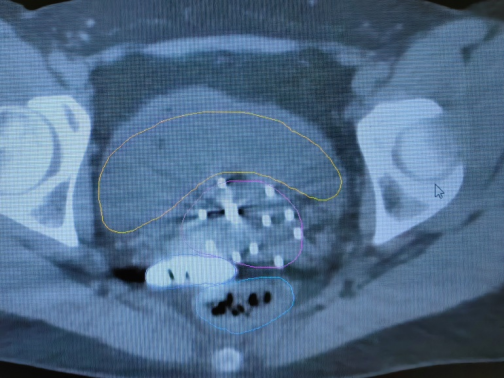

2. 無痛近距離插植治療:近距離插植治療是將宮腔管和插植針等施源器的置入宮頸及宮旁病灶組織的一種放療方式,由于老年患者陰道狹窄、對(duì)疼痛耐受性差,很多難以配合治療,甚至拒絕治療,導(dǎo)致腫瘤無法得到根治。我院婦科放化療采取靜脈麻醉下給予患者無痛插植治療,能夠最大程度上減少治療過程中患者的疼痛感和恐懼感,使得治療得以順利進(jìn)行,避免因中斷治療帶來的劑量缺陷,提高患者腫瘤的局部控制率,極大提高患者治療舒適度及依從性。

*無痛插值靶區(qū)